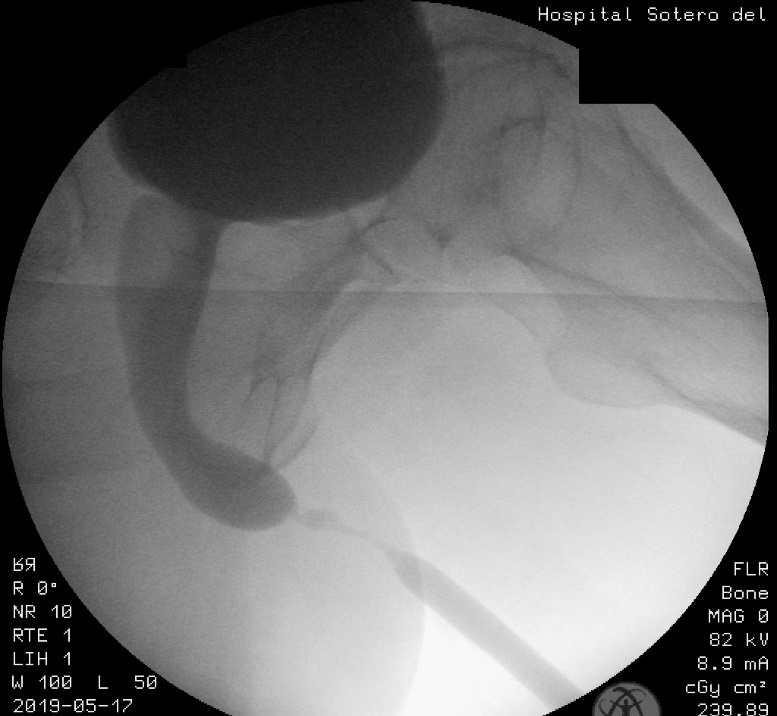

- La uretrocistografía retrógrada/miccional (UCG), es un examen dinámico que se realiza mediante la instilación uretral de contraste hidrosoluble bajo fluoroscopía y se recomienda que siempre sea hecha por el urólogo entrenado.20 Es el examen de elección para etapificación de las E/E. La UCG se encarga de definir la longitud, ubicación, severidad y número de las E/E. Además, da información sobre fístulas, duplicación uretral, falsa vía y el status del cuello vesical. El estudio completo consta de 2 fases: la fase retrógrada dibuja la uretra anterior y la fase miccional dibuja la uretra posterior, no siendo intercambiables, como se muestra en las imágenes.

La fase miccional debe hacerse con la mesa en posición vertical y el paciente con deseo miccional, haciendo el registro en forma continua. (Figura 6).